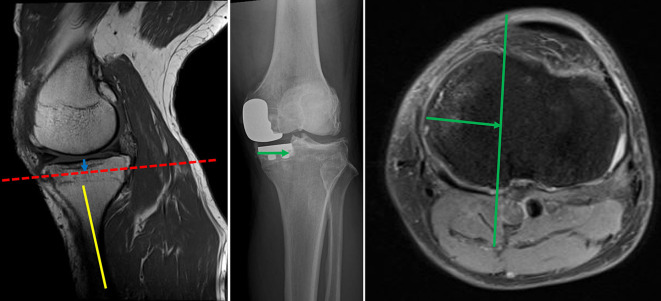

Methods: Preoperative MRI and postoperative radiographs obtained from 50 patients with unicompartmental KOA who underwent fixed-bearing UKA were analyzed. The amount of tibial resection was determined from the surgical records, and a line was drawn parallel to the tibial posterior tilt angle on the sagittal MR image to create a virtual tibial cut line. The tibial resection width measured from the anteroposterior image of the postoperative radiograph was projected onto the transverse plane containing the intersection between the virtual tibial cut line and the posterior tibial cortex, after which a line was drawn parallel to the medial or lateral intercondylar ridge. We then determined whether the PA was within an extension of the osteotomy area. The shortest distance (Distance 1) between the posterior tibial cortex and the PA within the osteotomy area was measured. In addition, the shortest distance between the line extending the osteotomy posteriorly and the PA was measured (Distance 2).

Results: The medial UKA (group M) and lateral UKA (group L) group comprised 41 and 9 cases. The percentage of PA located behind the osteotomy plane was significantly higher in group L than in group M [6/9 knees (66.7%) vs. 2/41 knees (4.9%); P < 0.001]. The distance 1 was 12.6 (4.3) mm in group M and 7.9 (3.7) mm in group L (P = 0.004). The distance2 was 11.1 (4.9) mm in group M and 2.6 (3.5) mm in group L (P < 0.001).